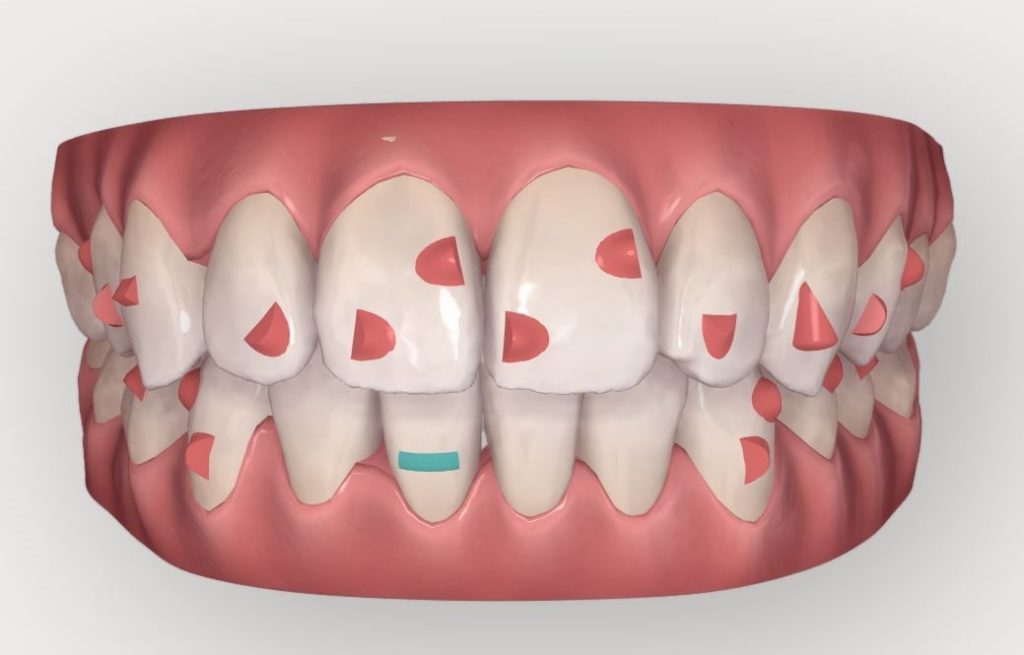

Un premier Clincheck fut réalisé, permettant de voir l’alignement souhaité et repositionner les dents selon le désir de la patiente.

On peut ici constater :

• Une série de 14 aligneurs

• Une série de réduction inter proximale maxillaire (RIP) pour un total de 1,5mm réparti entre les 15 et 25

• Une série de réduction inter proximale mandibulaire (RIP) pour un total de 0,9mm réparti entre les 15 et 25

• Des taquets répartis sur toutes les dents maxillaires pour optimiser les mouvements voulus

• Des taquets sur quelques dents maxillaires

Durée du traitement : 28 semaines, avec un changement des aligneurs toutes les 2 semaines.